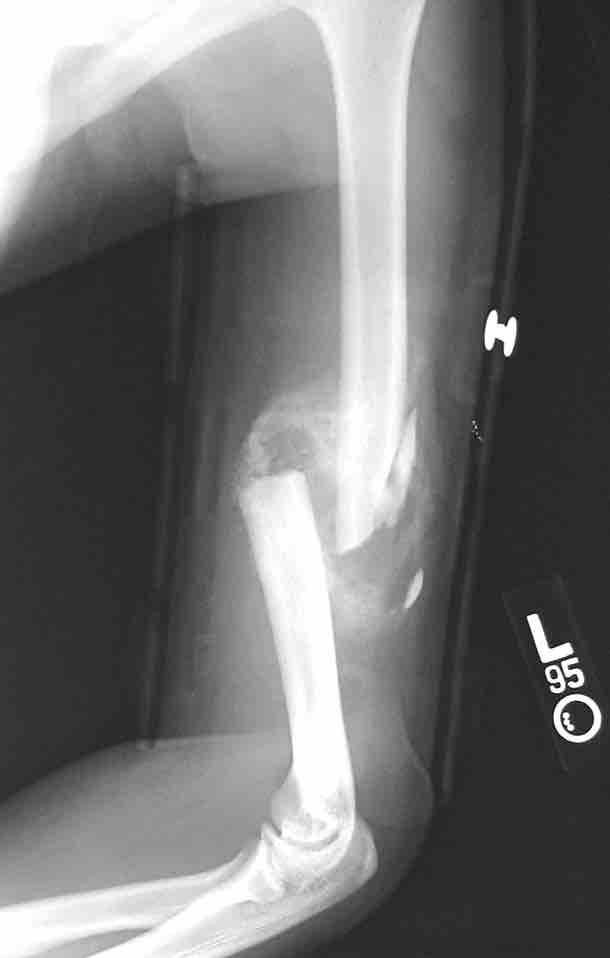

This figure depicts a communitive midshaft humeral fracture with callus formation.

This is an x-ray image of a broken arm. It shows a communitive midshaft humeral fracture with callus formation.